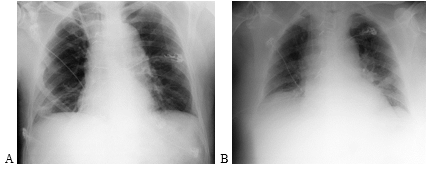

A 79-year-old man was admitted to St.Ekatherina UH with syncope and signs of progressive right ventricular dysfunction and respiratory failure. He had no comorbidities, only a history of lower leg trauma complicated by a subcutaneous infection a month ago. His vital signs were: saturation - 91%, tachypnea – 35 insp/min, tachycardia 150 b/min, and hypotension - 90/50mmHg. Transthoracic echocardiography revealed right ventricle dilatation with decreased systolic function and huge thrombotic mass free-floating in the right atrium, protruding through the tricuspid valve into the right ventricle in diastole (Figure 1).

Figure 1 Transthoracic echocardiography showing a mobile thrombus (white arrow) protruding to the right ventricle in diastole-apical view. LV- left ventricle; RV – right ventricle.